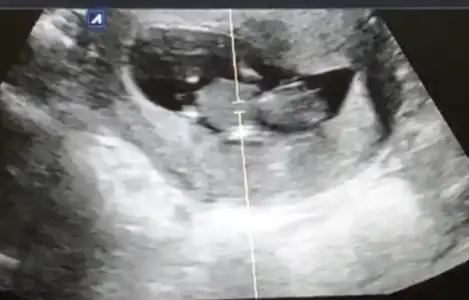

ay bende çok merak ediyorum 14haftalık usg bu acaba kız mı erkek mi olacak 😊 doktor bacaklarını açmıyor dedi 2 hafta sonrada çağırdı kesin Konuşuruz dedi ama ben duramıyorum meraktan

Nubu net değil sanki erkek gibi bilemedim ben 11 12 13 haftalara bakıyorum 14 de organı oluşuyor çunki